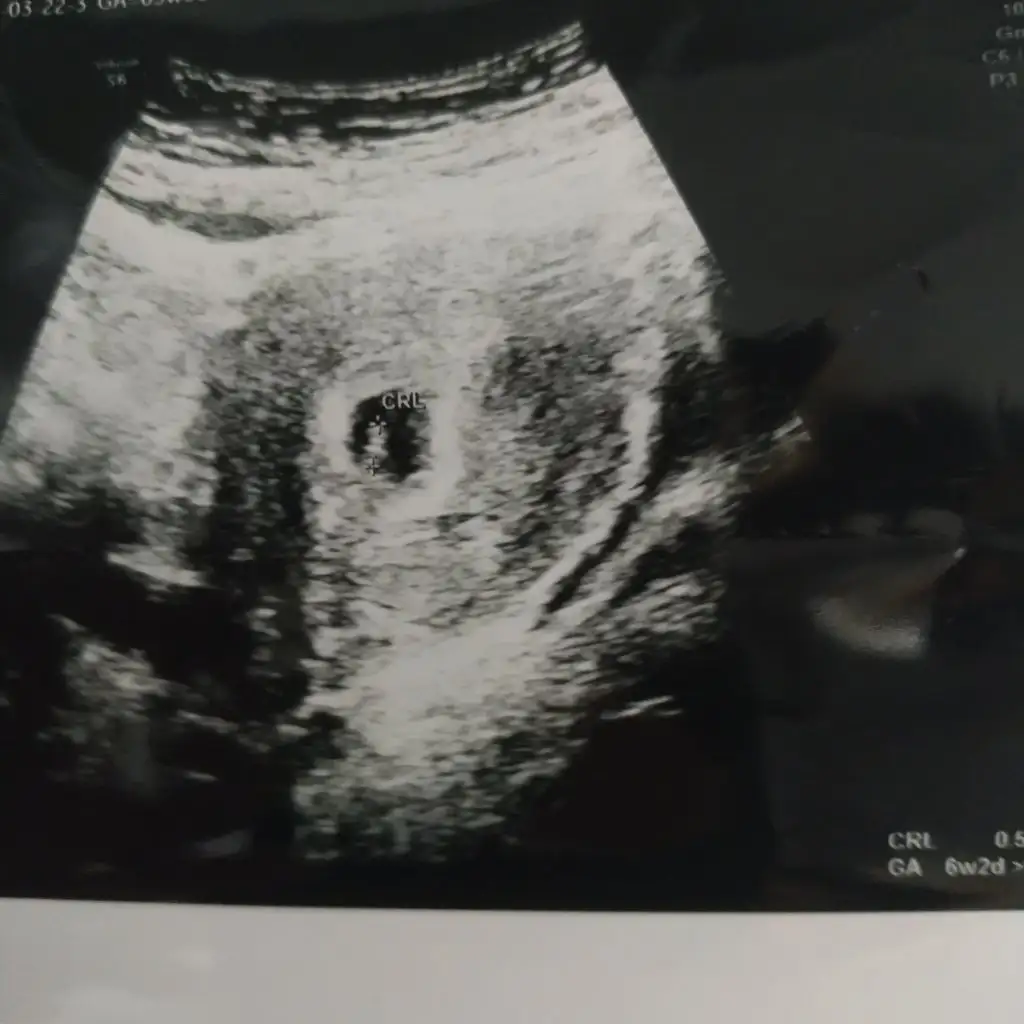

Ramzi teorisine göre cinsiyet tahmini yapacagim ilk ultrasyon resminizi atin bakiyim. Eger cinsiyetiniz belliyse hic söylemeeyin bakalm dogru tahmin edebilecekmiyim daha dogrusu ramzi teorisi hakli cikacak mi?

6+2 karından ultrason banada tahminde bulunabilirmisniz

Emin olmamakla birlikte kiz .şu anda kaç haftaliksinizEki Görüntüle 3066106 6+0 karından